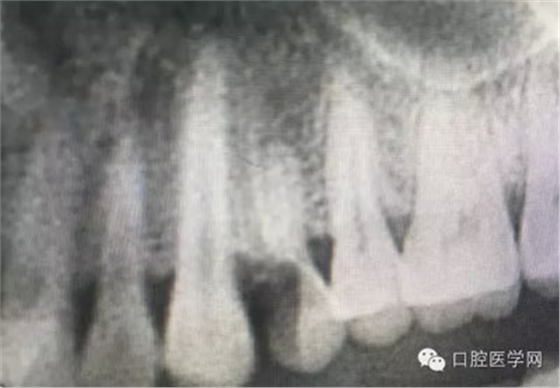

根管治療,我們?cè)诖髮W(xué)的時(shí)候就學(xué)習(xí)的東西,標(biāo)準(zhǔn)就在那里放著,可是很多時(shí)候我們熟視無睹,放任我們的想象去做。我們多些重視,多些心思,會(huì)好很多,認(rèn)真對(duì)待每顆牙齒。